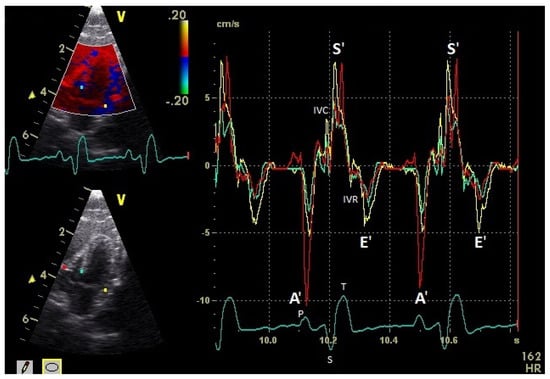

Figure 4.

Myocardial velocities of the left ventricular free wall in the four-chamber view measured by TDI (sample areas: Ø 2 mm). The tissue velocities of the basal (yellow), middle (green), and apical (red) segment are shown: early diastolic: E’ wave; late diastolic: A’ wave; systolic tissue velocities: S’ wave. Isovolumetric contraction: IVC; isovolumetric relaxation: IVR; HR: heart rate. Electrocardiogram: P: P wave; S: S wave; T: T wave.

The positive S’ wave of the TDI curve (Figure 3 and Figure 4; ascending part of the S wave to the descending part of the T wave of the ECG) describes the systolic movement of the heart base toward the heart apex and represents the expulsion phase of the heart. In the middle of the S’ wave of the TDI, there is little movement of the heart apex toward the heart base and the myocardial velocities are negative (Figure 2). This movement in the middle part of the systole led to an irregular shape of the S’ wave in the TDI curve (Figure 3). The negative E’ wave (Figure 3 and Figure 4; after the T wave of the ECG) in the TDI curve describes the movement of the myocardium during the passive ventricular filling and the second negative A’ wave of the TDI curve (Figure 3 and Figure 4; P wave of the ECG) describes the movement of the myocardium in the active filling phases of the heart during the diastole away from the heart apex. Before and after the S’ wave, the TDI curve showed undirected deflections as a sign of isovolumetric contraction (IVC) and relaxation (IVR; Figure 3 and Figure 4). However, the transition between the A’ and S’ waves (IVC) and the S’ and E’ waves (IVR) could be flowing and sometimes difficult to see.

The systolic and diastolic peak tissue velocities depending on the myocardial segment are shown in Table 1. In general, the highest myocardial velocities are visible at the atrioventricular valvular annulus in the basal segments. The velocities decrease significantly and continuously to the apex of the heart for the S’, E’, and A’ waves (p ≤ 0.001). Significant differences in the myocardial velocities could also be detected between the heart septum and the left and right free wall (Table 1).